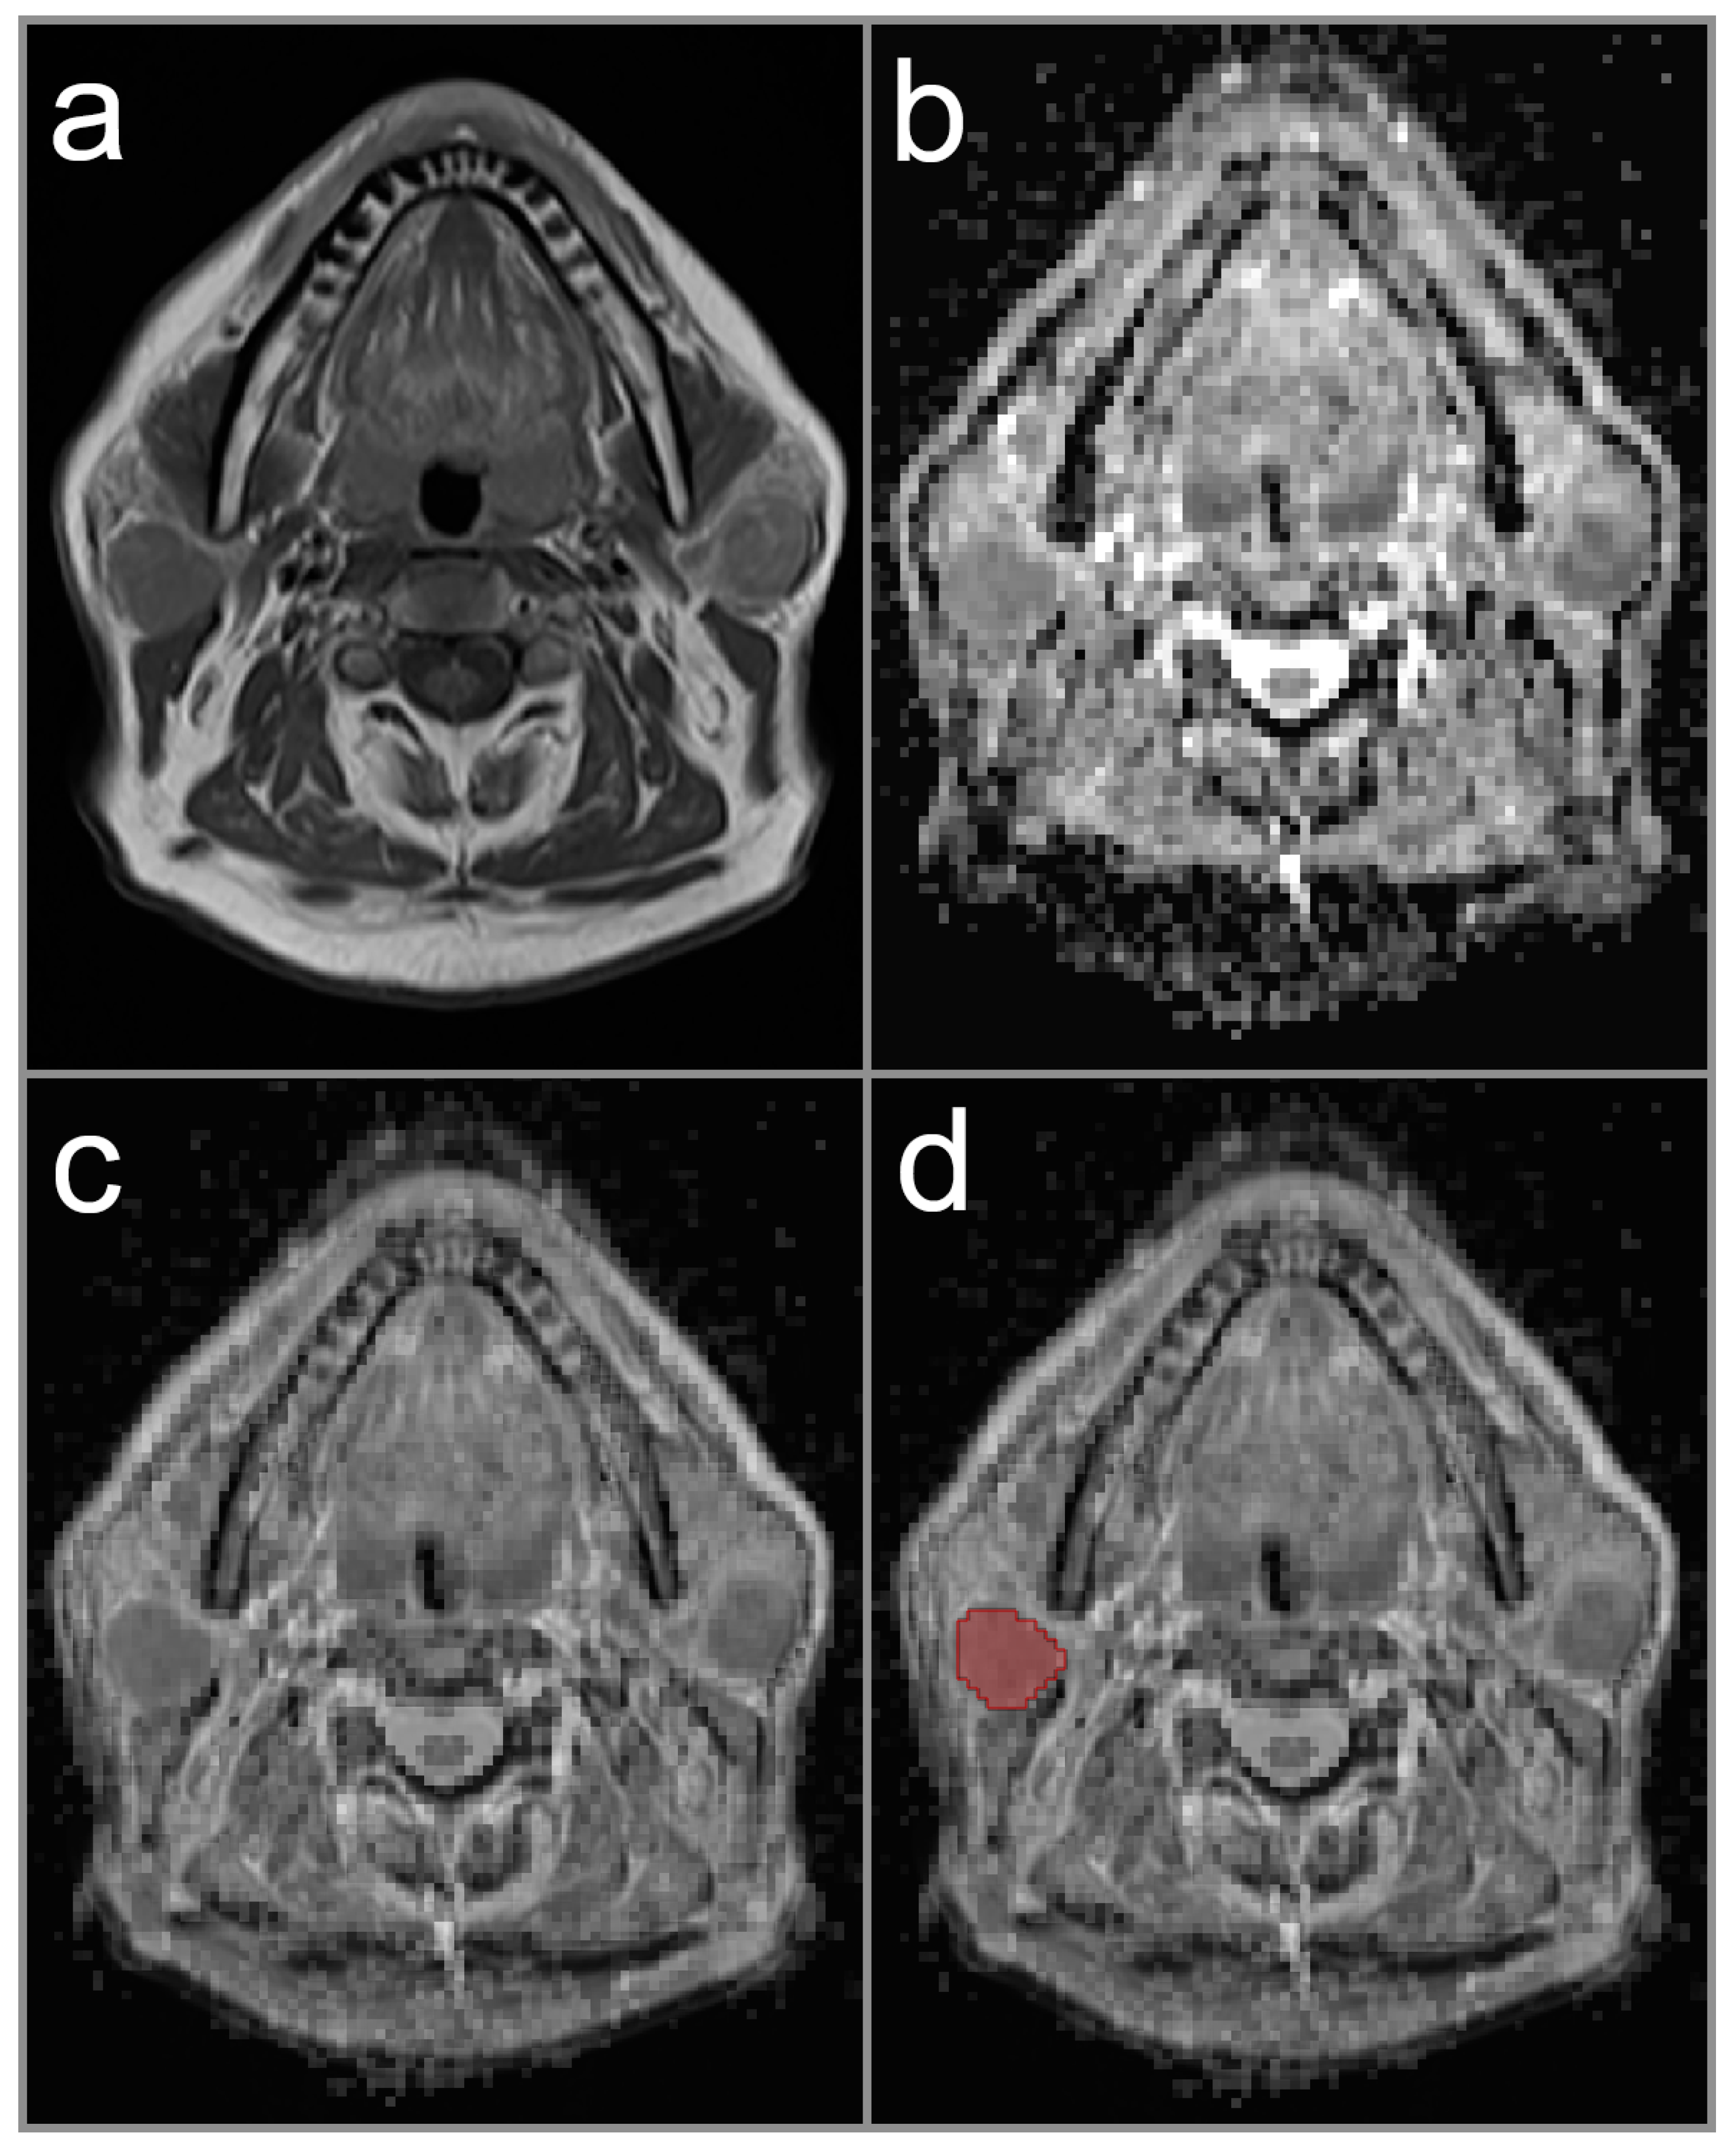

2.3. Image Analysis and ADC Measurement